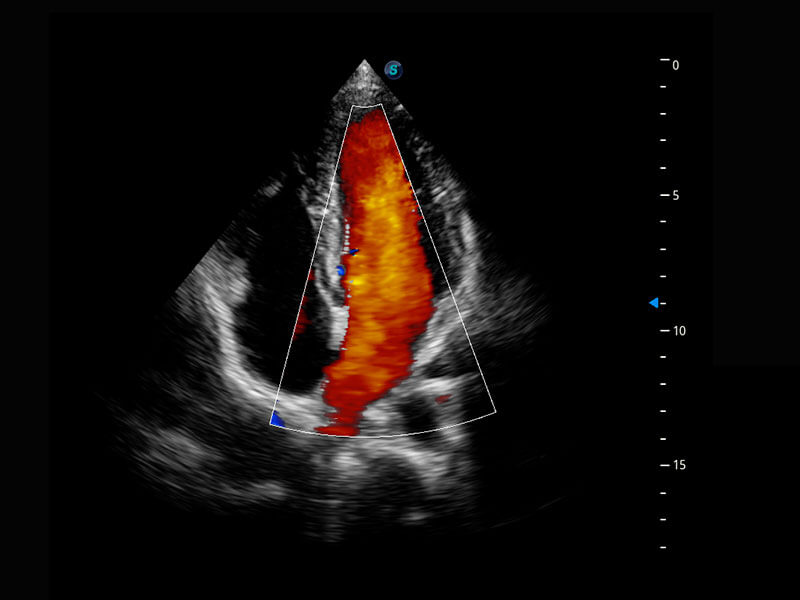

P60搭載寬頻帶線陣探頭、寬景成像、彈性成像技術(shù),為您提供乳腺應(yīng)用方案。P60支持高頻相控陣探頭、線陣探頭、腹部高頻探頭、腹部微凸探頭等,豐富的探頭群搭載敏感的彩色血流成像,適用于新生兒多種臟器檢測(cè)要求,滿足新生兒篩查需求。

新生兒心臟